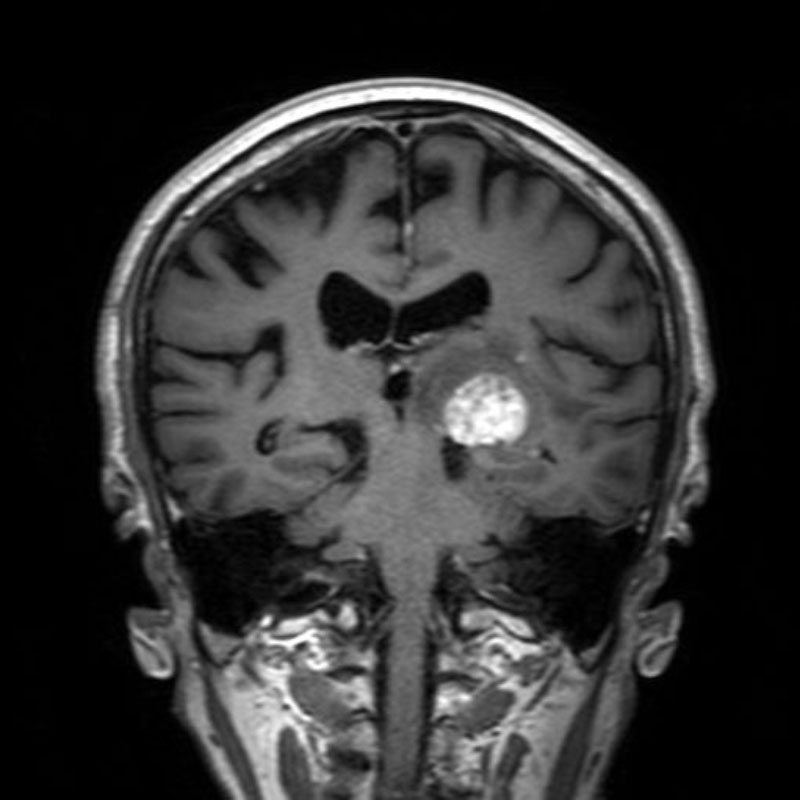

断層撮影

手術前1

手術前2